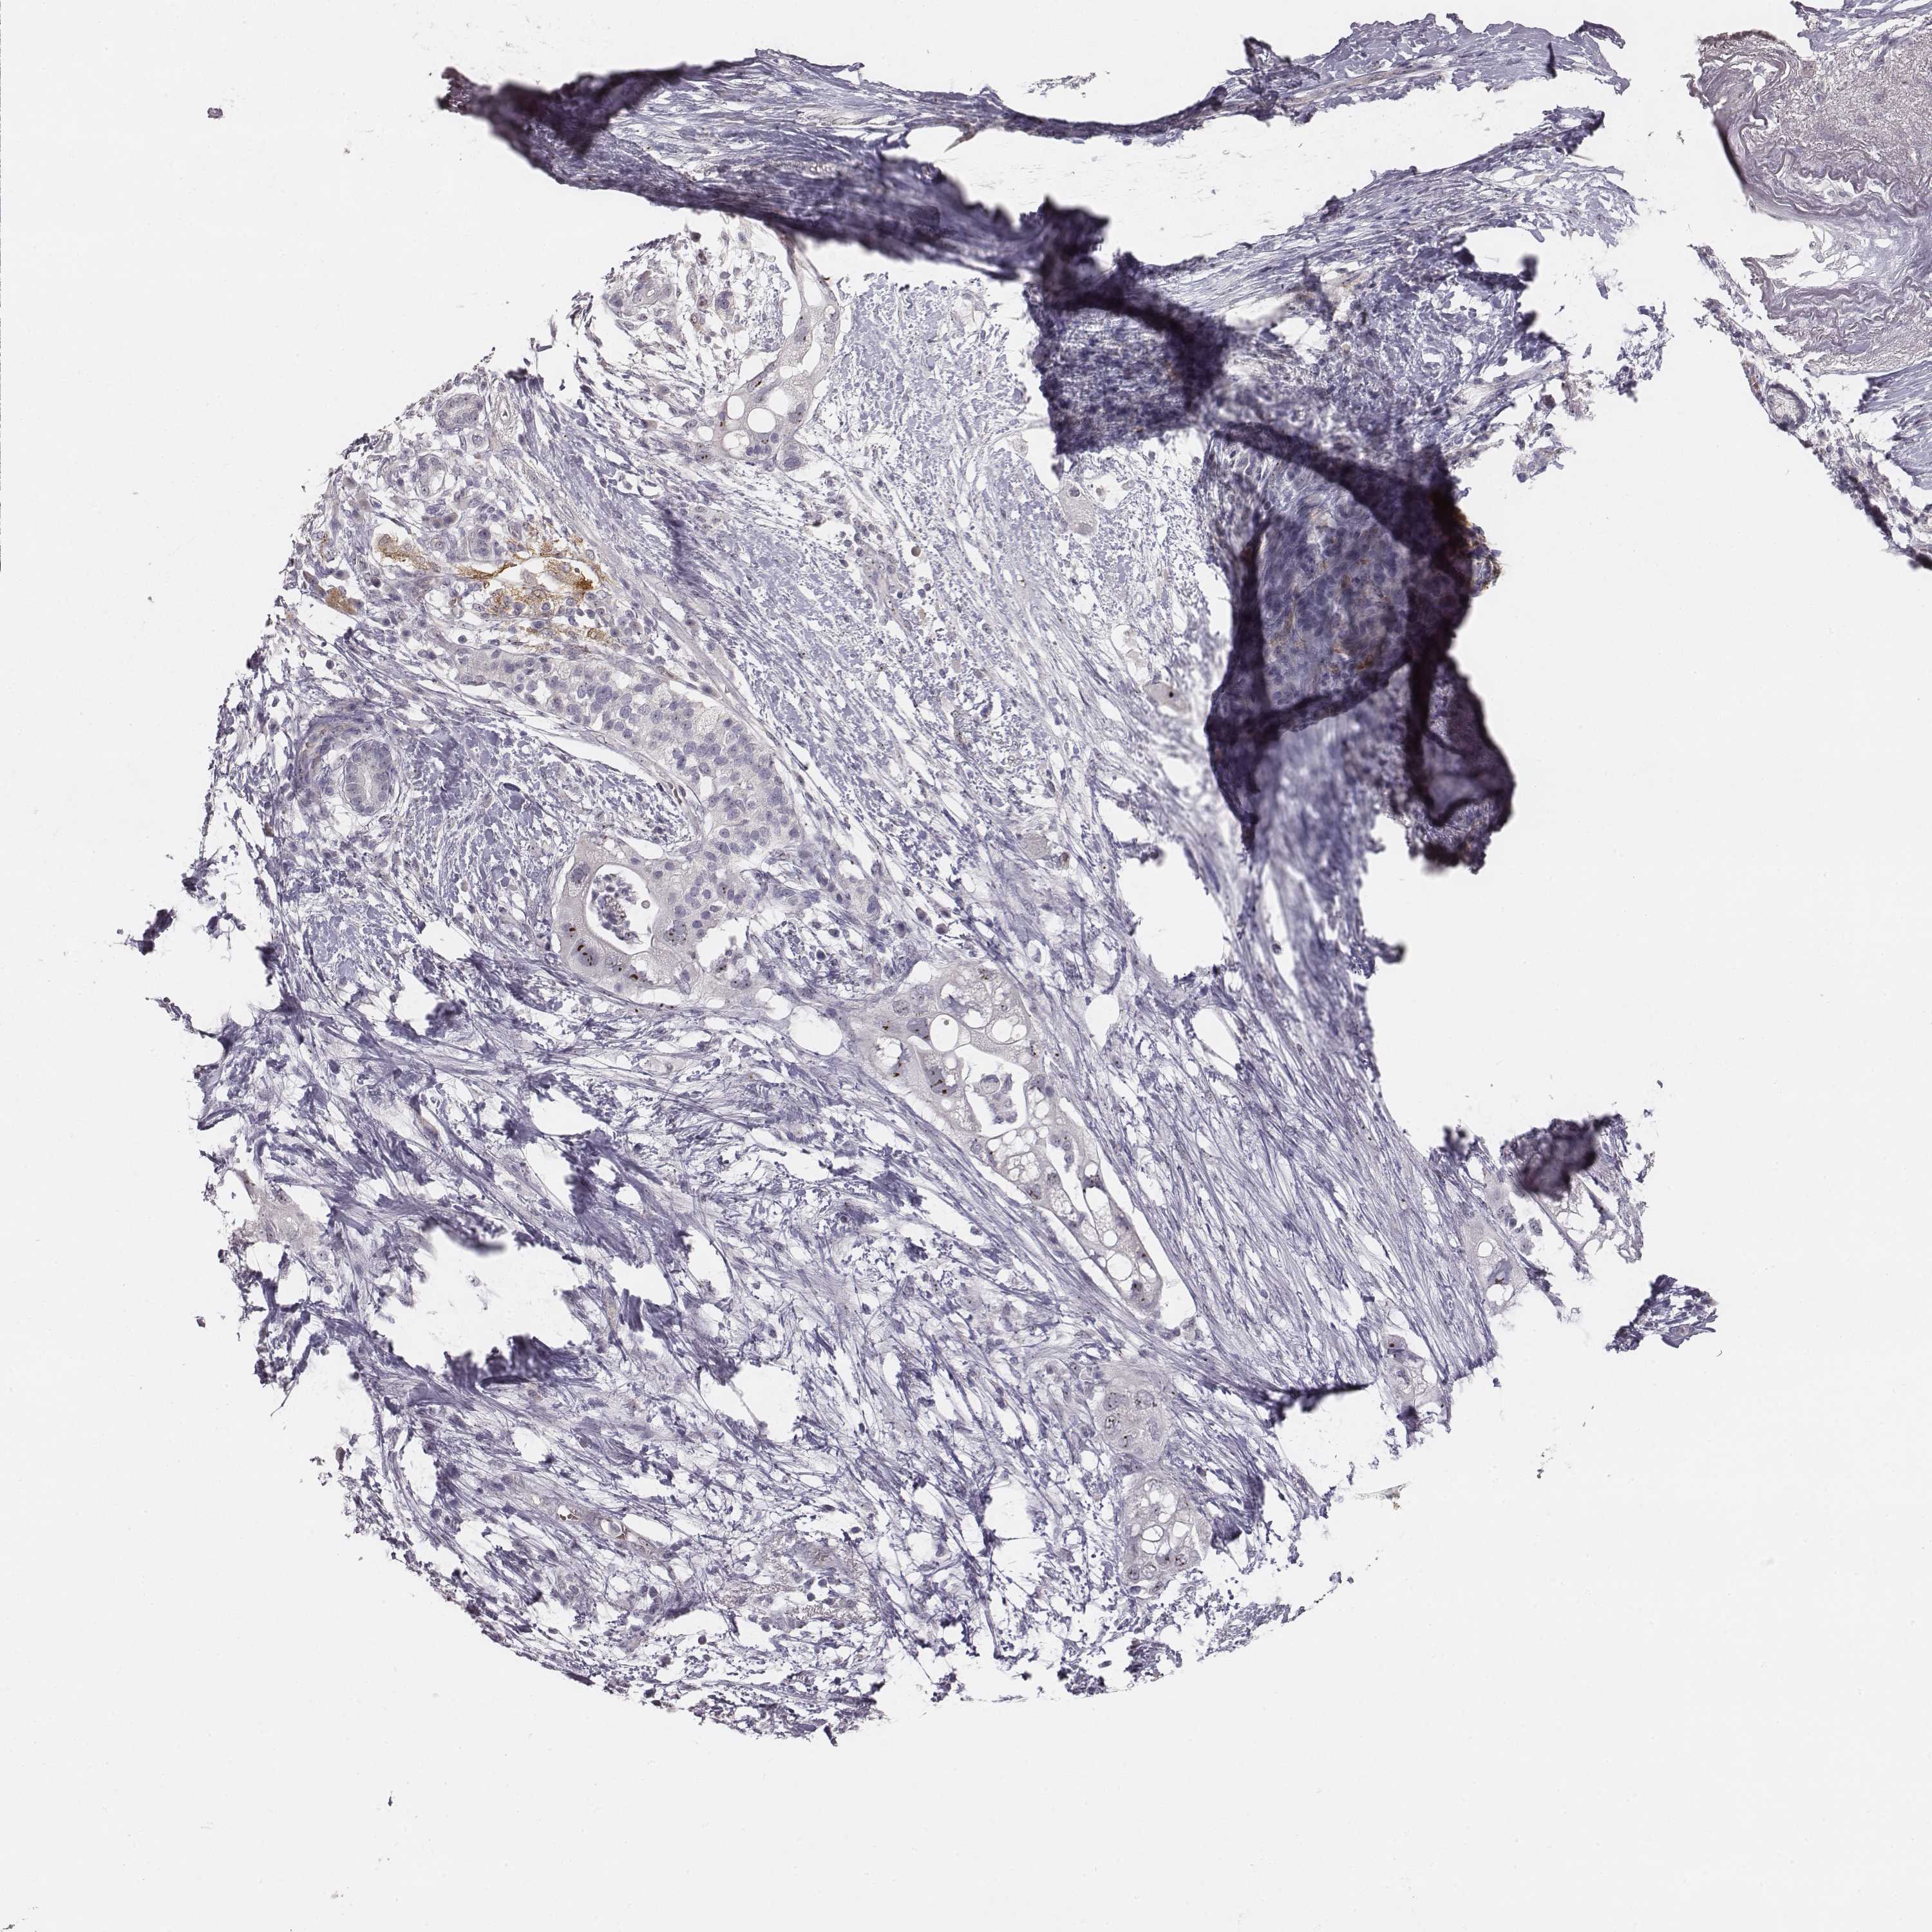

PANCREATIC CANCER - Protein expressioni

A mouse-over function shows sample information and annotation data. Click on an image to view it in a full screen mode. Samples can be filtered based on level of antibody staining by selecting one or several of the following categories: high, medium, low and not detected. The assay and annotation is described here.

Note that samples used for immunohistochemistry by the Human Protein Atlas do not correspond to samples in the TCGA dataset.

Antibody stainingi

Antibody staining in the annotated cell types in the current human tissue is reported as not detected, low, medium, or high, based on conventional immunohistochemistry profiling in selected tissues. This score is based on the combination of the staining intensity and fraction of stained cells.

Each image is clickable and will lead to virtual microscopy that enables deeper exploration of all samples and also displays staining intensity scores, fraction scores and subcellular localization as well as patient and tissue information for each sample.

HPA035735

HPA035736

CAB015382

CAB075728

CAB075729

Staining

High

Medium

Low

Not detected

Intensity

Strong

Moderate

Weak

Negative

Quantity

>75%

75%-25%

<25%

None

Location

Nuclear

Cytoplasmic/membranous

Cytoplasmic/membranous,nuclear

Adenocarcinoma, NOS